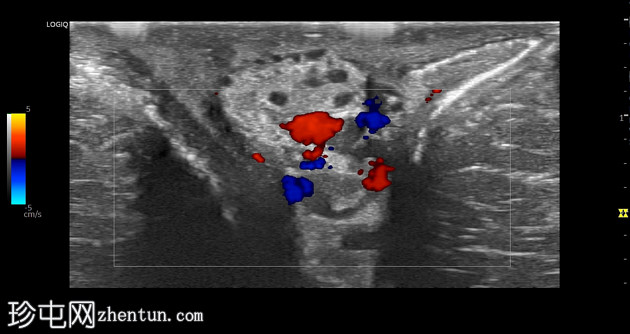

左侧阴囊精索静脉曲张。左侧蔓状静脉丛多条扩张,部分静脉内可见回声增强内容物,彩色多普勒显示血流信号消失。

阴囊精索静脉曲张是睾丸疼痛的常见原因。然而,以精索静脉曲张血栓形成为主要表现的急性病例较为罕见。超声显示,静脉扩张,内含回声增强内容物,不可压缩,彩色多普勒显示血流信号消失。触痛是另一项临床体征。